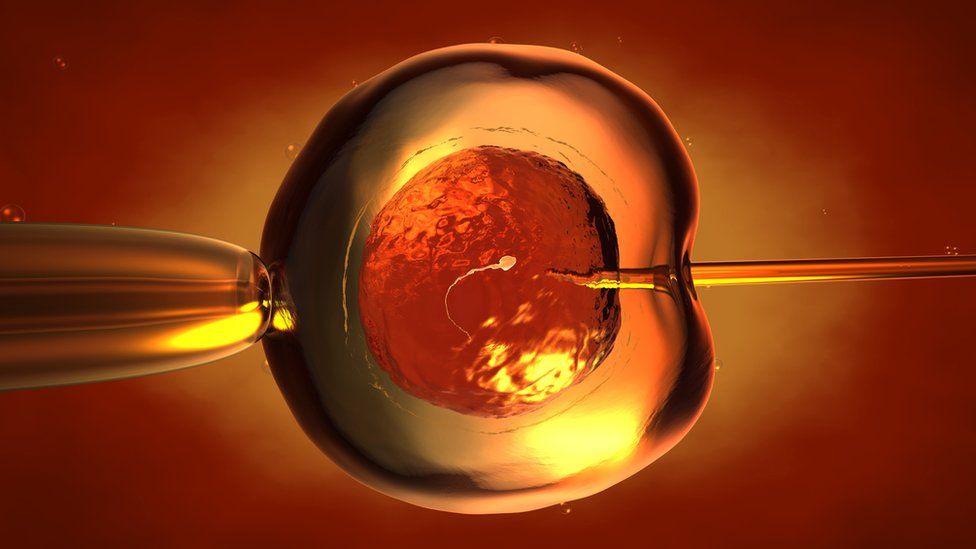

Un grupo de Izpisúa, repartido entre el Instituto Salk de EE.UU. y la UCAM, logró modificar genéticamente embriones de mono para inactivar genes esenciales para la formación de sus órganos. Los científicos inyectaron células humanas capaces de generar cualquier tipo de tejido.

Según informó Estrella Núñez, bióloga y vicerrectora de investigación de la Universidad Católica de Murcia (UCAM), el equipo del investigador Juan Carlos Izpisúa logró de esta forma un gran avance hacia su objetivo final, que es el de convertir animales de otras especies en fábricas de órganos para trasplantes.